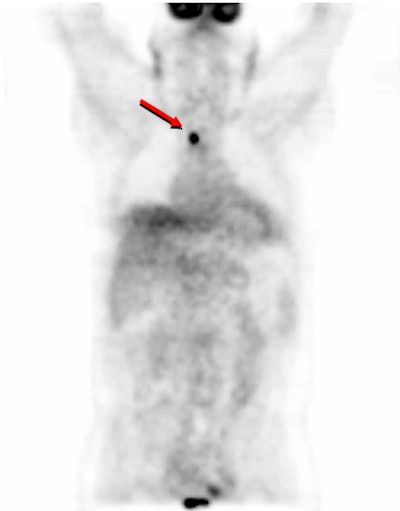

| A 60-year-old patient with recurrent head and neck cancer and body weight of 225 lb. (102 kg.) presents with a 1.5 cm superior mediastinal lymph node cancer (red arrow) in an image obtained at three minutes during an upper-body PET scan. Image courtesy of the Society of Nuclear Medicine and the Ahmanson Clinic for Biological Imaging at the UCLA School of Medicine. |

The researchers prospectively compared PET image quality and lesion detectability using 1-, 2-, 3-, and 4-minute PET images obtained in the same patient in a total of 32 patients. Each patient was injected with 0.21 mCi/kg of FDG and underwent a whole-body standard CT scan (45 seconds). PET emission data was acquired at 4 minutes per bed position for 24 patients, and at 3 minutes per bed position for 8 patients.

The group found that for patients weighing less than 130 lbs (59 kg), the 1-minute scans per bed position provided the same diagnostic information as the 2-, 3-, and 4- minute scans. For the subgroup of patients weighing between 130 and 179 lbs (59-82 kg), the 2-minute scans provided the same diagnostic information as the 3- and 4- minute scans. For the largest group of patients, who weighed between 180 and 249 lbs (82-113 kg), the 3-minute scans provided the same diagnostic information as the 4-minute scans.